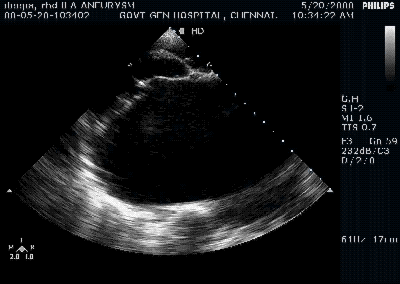

Rheumatic mitral valve prolapse

- This could be more common than we realise.

- It can be true or pseudo.

- True prolapse occur due to chordal weakening or lengthening .

- In chordal disruption the leaflet tips usually become flail

Since rheumatic process fixes the PML first , the AML appear to overshoot the plane of PML and appear as prolapse.(Pseudo )

The sail like AML commonly directs the jet posteriorly and laterally .(Murmur conducted to axilla and back )

It is rare for PML to prolapse in RHD , if it does occur , it directs the jet anteriorly (murmur conducted to aortic area mimic AS !)

It is rare to see a perfect central jet in RHD . presence of Central jet is a good sign to consider mitral valve repair.